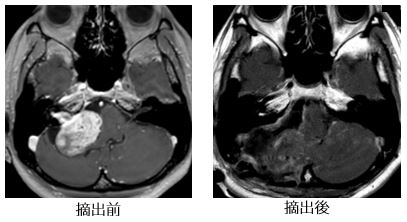

代表的な良性脳腫瘍のひとつです。脳神経を取り巻く膜から発生し比較的ゆっくりと成長しますが、大きくなると神経症状や脳の圧迫症状を起こします。最も頻度が多い神経鞘腫は前庭神経鞘腫(聴神経腫瘍)で、耳鳴りや難聴、めまいなどを発症します。三叉神経、顔面神経、下位脳神経などにもできることがあります。大きな腫瘍の場合には手術による摘出が治療法の第一選択となりますが、小型の場合には成長速度をみながら経過観察することも選択肢の一つとなります。聴神経腫瘍の手術では聴力温存や顔面神経温存のために、顔面神経刺激装置やABRといった術中神経モニタリングを活用します。